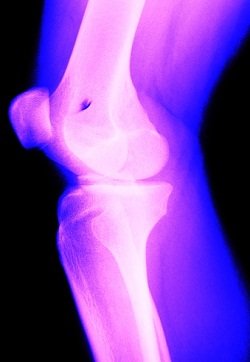

관절내시경 수술은 관절 피부에 0.5cm의 작은 구멍을 내어 초소형 카메라가 달린 내시경을 삽입한 뒤 관절 안의 모습을 화면으로 보면서 진단과 수술을 시행하는 방법이다.

'수술’하면 두려움을 갖기 쉽지만 관절내시경 수술은 절개를 하지 않고 국소마취로 시행하여 수술에 대한 부담감 또한 최소화했다. 또한 흉터나 출혈 걱정이 거의 없고 회복기간이 빨라 어린 학생, 직장인 및 고령의 노인들까지 안심하고 받을 수 있다. 가장 큰 특징으로는 자기 관절을 최대한 보존하며 병변 부위를 직접 치료하기 때문에 근본적인 관절의 통증 개선이 가능하다는 점이다.